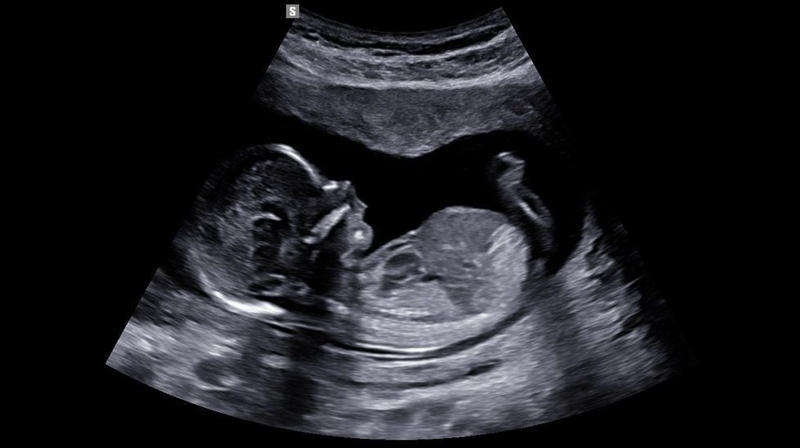

Siêu âm là kỹ thuật y khoa giúp chẩn đoán hình ảnh giúp theo dõi sự phát triển của thai nhi trong bụng mẹ. Siêu âm có thể giúp đo chiều dài xương mũi của thai nhi. Vậy liệu siêu âm có biết được mũi cao hay thấp không?

Siêu âm có biết được mũi cao hay thấp không? Nếu bạn đang mang thai và băn khoăn về việc xác định chiều dài xương mũi của thai nhi, việc tham khảo ý kiến bác sĩ để lên lịch kiểm tra là điều cần thiết. Kết quả từ những lần kiểm tra này sẽ giúp bác sĩ dự đoán các nguy cơ tiềm ẩn và đưa ra hướng dẫn chăm sóc sức khỏe phù hợp cho thai nhi.

Xương mũi thường hình thành vào tuần thứ 12 của thai kỳ, và chiều dài đầu mông của thai nhi thường đạt khoảng 64 - 75 mm, đây là thời điểm lý tưởng để đánh giá chiều dài xương mũi. Việc theo dõi chỉ số này sẽ tiếp tục đến khi thai nhi được 28 - 32 tuần tuổi.

Chiều dài xương mũi của thai nhi thường được đánh giá vào tuần thai thứ 12, khi xương mũi đã hình thành và chiều dài đầu mông của thai nhi đạt khoảng 64 - 75 mm. Đây là thời điểm lý tưởng để kiểm tra chiều dài xương mũi. Việc theo dõi chỉ số này nên được duy trì cho đến khi thai nhi được 28 - 32 tuần tuổi.